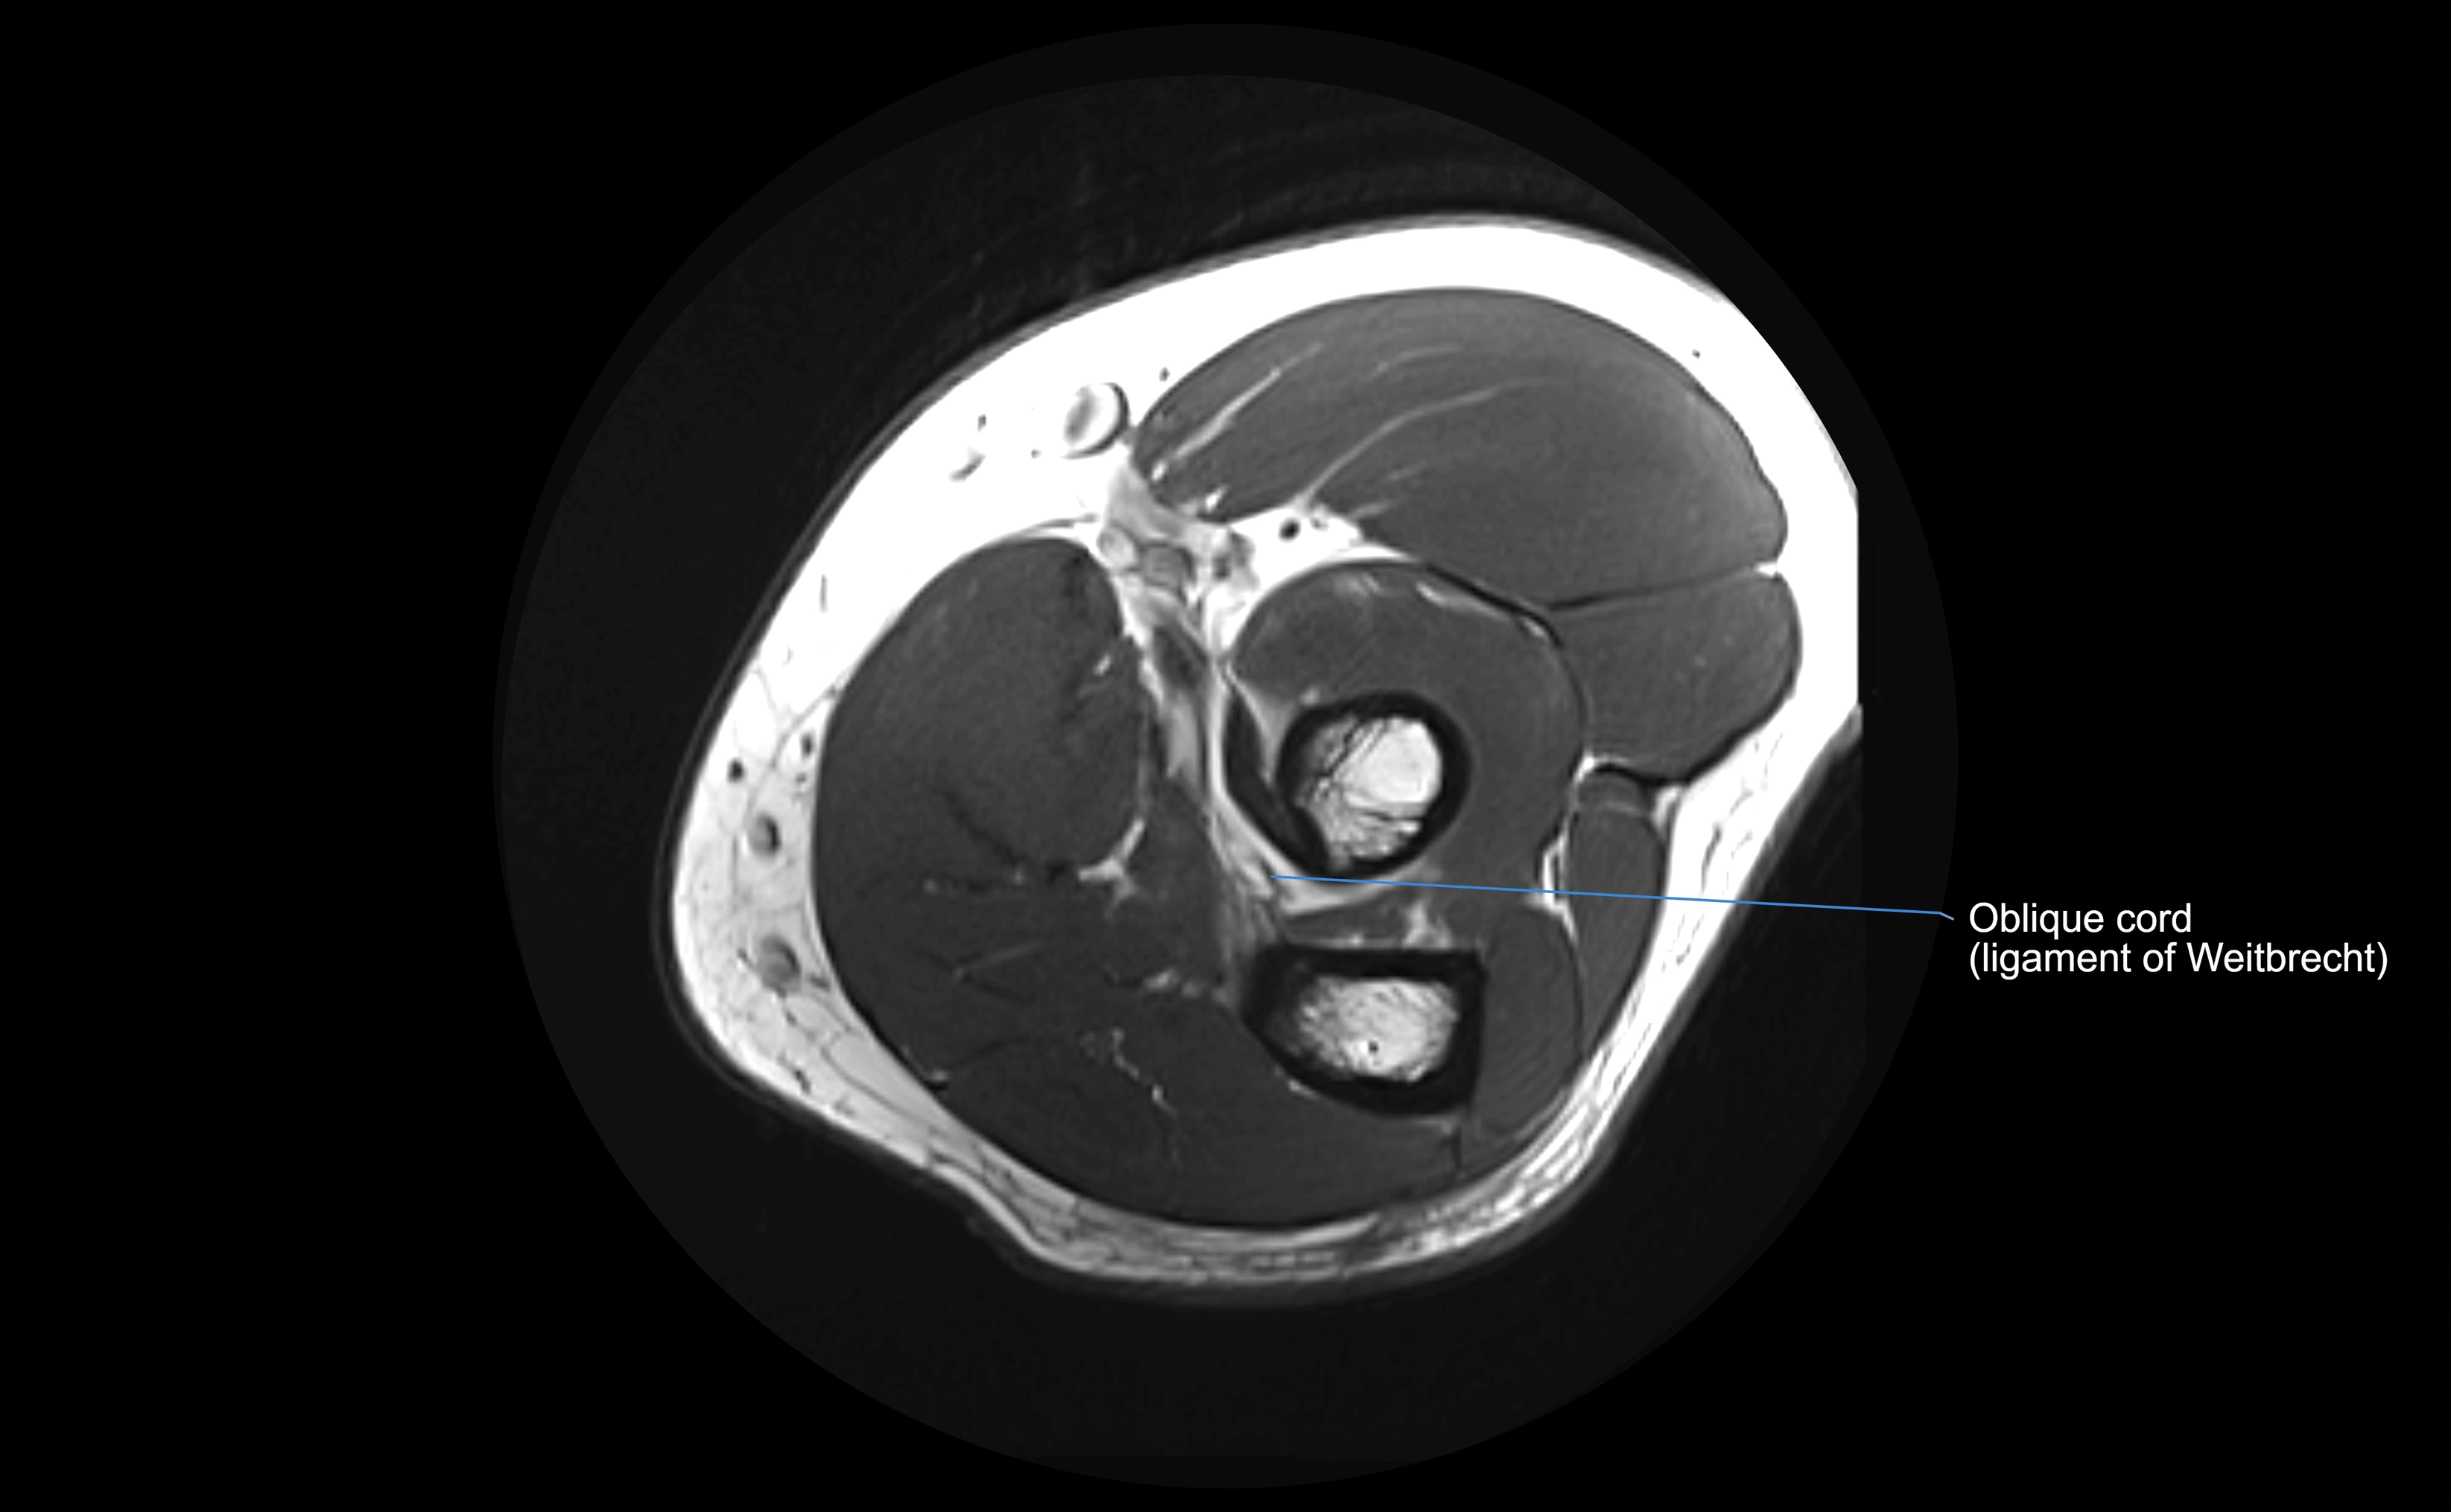

MRI images

image